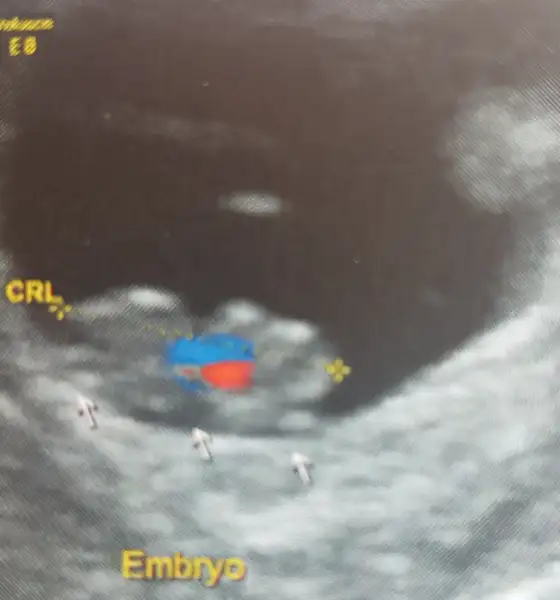

Ah yavrum nasıl da tatlılar ya, şükürler olsun ben dün hem sana hem kendime dua etmiştim:) benim de bugün randevum vardi. hatta bebegi biraz daha net gördük. kanama alanı da düzelmis şükürler olsun ki. şaşkına döndüm gecen hafta 7.5mm idi bugün 1.5cm olmuş. 2 katina çıkmış. kalbi de 129 atiyordu 157 ye cikmiş :) hatta usg yi de paylasıyorum, masallah hepsinekizlar biz gorduk kuzumu. kalbini ekranda kipir kıpır halini sesini dinledik. ekranda gorunce Rabbime binlerce kere şükür ettim. Darisi bekleyenlere.

maşallah kuzuya. ay ne heyecan vardi anlatamam. hosgeldin dedi dr. titreye titreye geldim hocam dedim. gel gel insallah guzel olur sonuc dedi. ama ekranda kıpır kıpır kalbi gorunce sukurler olsun dedim.Ah yavrum nasıl da tatlılar ya, şükürler olsun ben dün hem sana hem kendime dua etmiştim:) benim de bugün randevum vardi. hatta bebegi biraz daha net gördük. kanama alanı da düzelmis şükürler olsun ki. şaşkına döndüm gecen hafta 7.5mm idi bugün 1.5cm olmuş. 2 katina çıkmış. kalbi de 129 atiyordu 157 ye cikmiş :) hatta usg yi de paylasıyorum, masallah hepsine